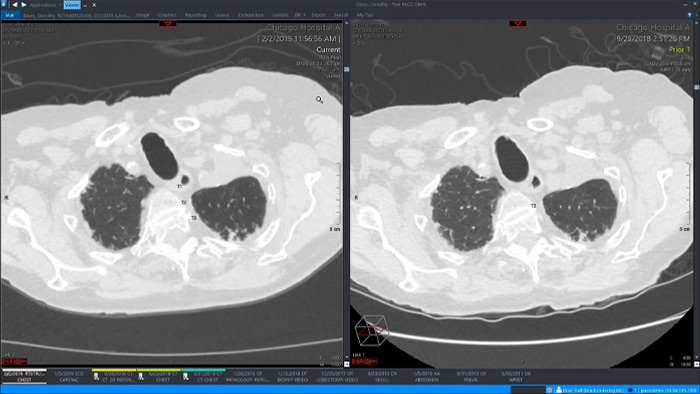

Let’s take a look at some of the immediate benefits of a unified approach. A single, unified workspace for radiology would incorporate advanced 3D post-processing and image distribution capabilities, opened in an additional viewer tab for ease.

A unified workspace would mean that users can easily launch the relevant analysis tools from among the 70+ advanced applications available across multiple clinical domains. Artificial Intelligence can play a role by automating tasks and workflows, predicting usage patterns.

An all-in-one workspace, fully integrated with the enterprise imaging platform and embedded in the diagnostic viewer, offers simple, efficient access to all needed tools across clinical domains. One-click access to advanced visualization tools – such as virtual colonoscopy, 3D processing, and spectral imaging – allows for efficient interpretation and supports diagnostic confidence.

Offers advanced visualization with a robust set of tools for AI-assisted quantitative assessment and automatic results generation.